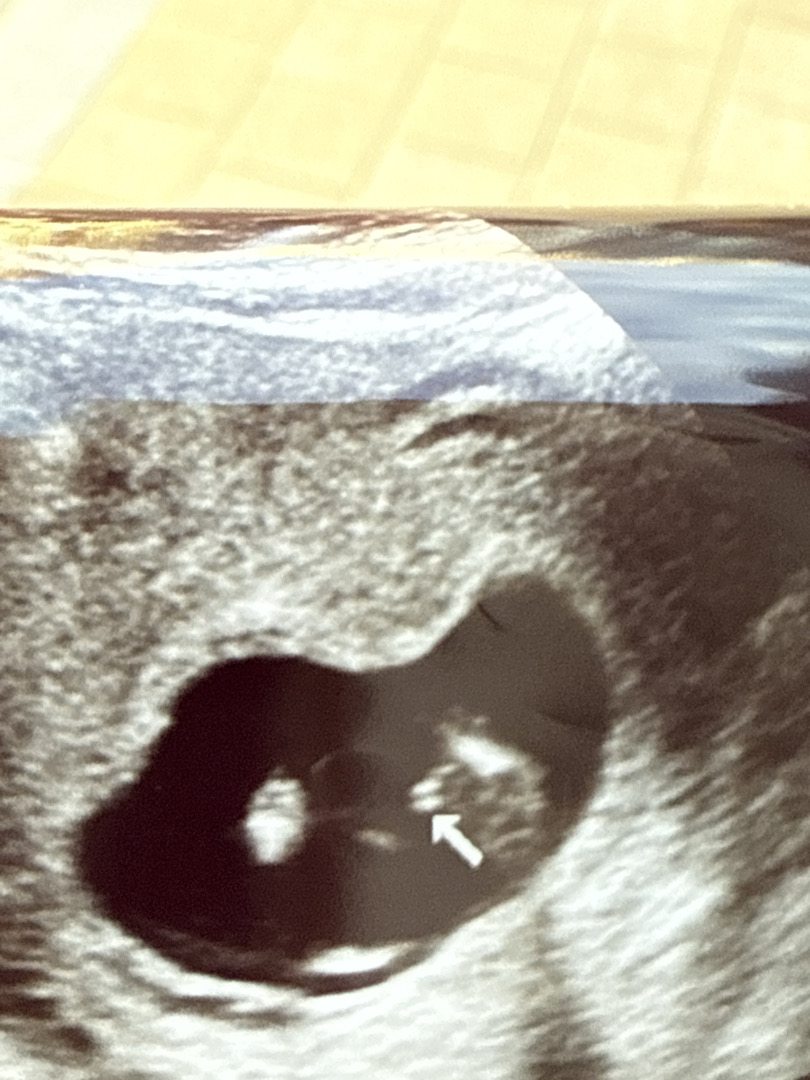

14주 성별 한번씩 투표 부탁드려요~❤️

의사선생님이 바뀔순있지만 아들같다고 하셨거든요?! 다른 엄마분들 눈에는 오또케 보이시나요!! 첫째가 딸이라 신랑이 아들 원하고 있는데 얼른 말해주고싶어서 ㅋㅋㅋㅋ!!